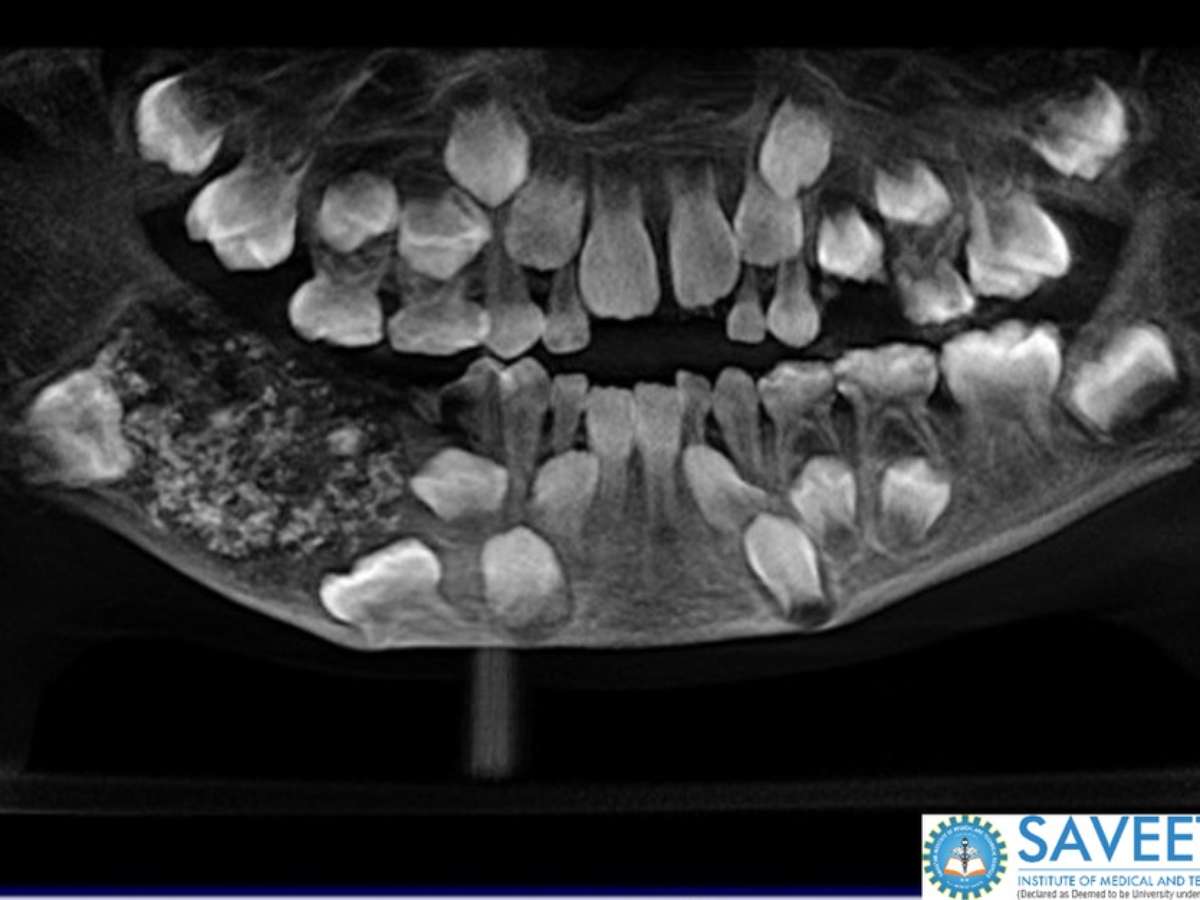

Exame de imagem mostra má-formação na dentição de garoto com odontoma composto

Foto: Saveetha Dental College and Hospital / Divulgação

Um menino indiano de 7 anos foi levado ao hospital pelos pais com queixa de inchaço no maxilar. Na época, em 2019, ele foi avaliado e, com ajuda de exames de imagem, foi comprovado que ele tinha uma grande lesão com múltiplas estruturas rígidas em um único local na mandíbula.